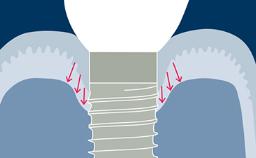

A geometria do corpo dos implantes geralmente pode ser dividida em três partes: a parte endóssea, que se encontra dentro do osso, a seção transmucosa, que fica nos tecidos moles entre o osso e a cavidade oral, e a interface com os componentes protéticos. Em cada uma dessas três partes, existem outras características da geometria e variações na sua forma, atributos e dimensões. Existem também variações no material do corpo do implante e no tratamento de superfície. Essas variações serão descritas e discutidas nos seguintes Objetivos de Aprendizagem.

- descrever as variações na parte endóssea do implante